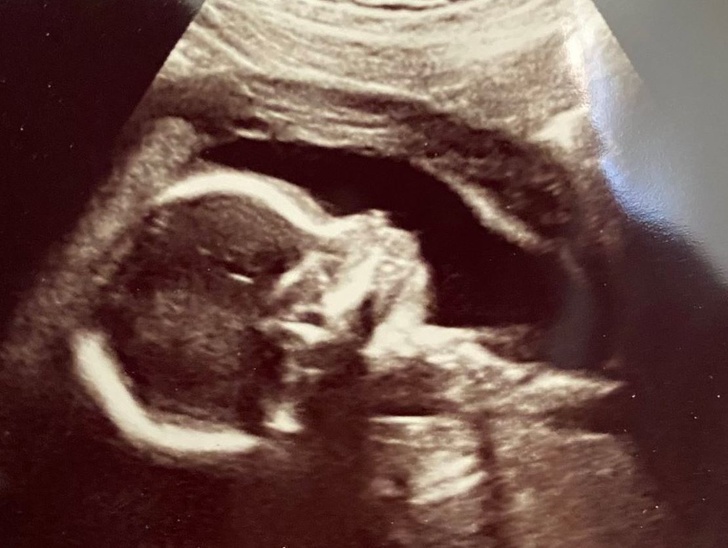

«Перше фото моєї дочки. Скоро ми зустрінемося»